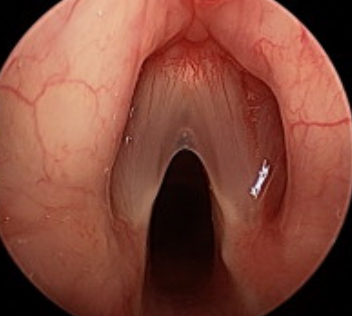

Структуры пазух носа, также называемые придаточными пазухами носа, представляют собой 4 пары воздушных пространств, расположенных внутри лицевых костей, и каждая названа в честь костных структур, в которых они расположены (верхнечелюстная, решётчатая, лобная и клиновидная пазухи). Пазухи, которые частично присутствуют при рождении, почти полностью развиваются примерно к 12-14 годам. Он имеет такие функции, как увлажнение вдыхаемого…